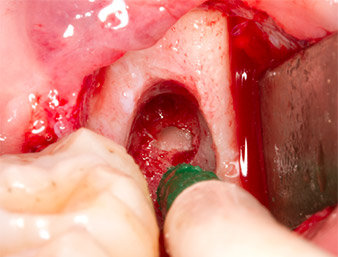

The tissue above the root remnant was not completely ossified and consisted for the most part of granulation tissue modified by inflammation (Fig. 4).

To obtain autogenous material for subsequent wound treatment, healthy bone chips were harvested from the surroundings of the root remnant with a piezo surgical instrument (Piezomed B5) (Fig. 5).

The autogenous tissue was removed with the scraper-shaped section of the working part of the instrument and stored in a physiological saline solution until further use (cf. Fig. 13).